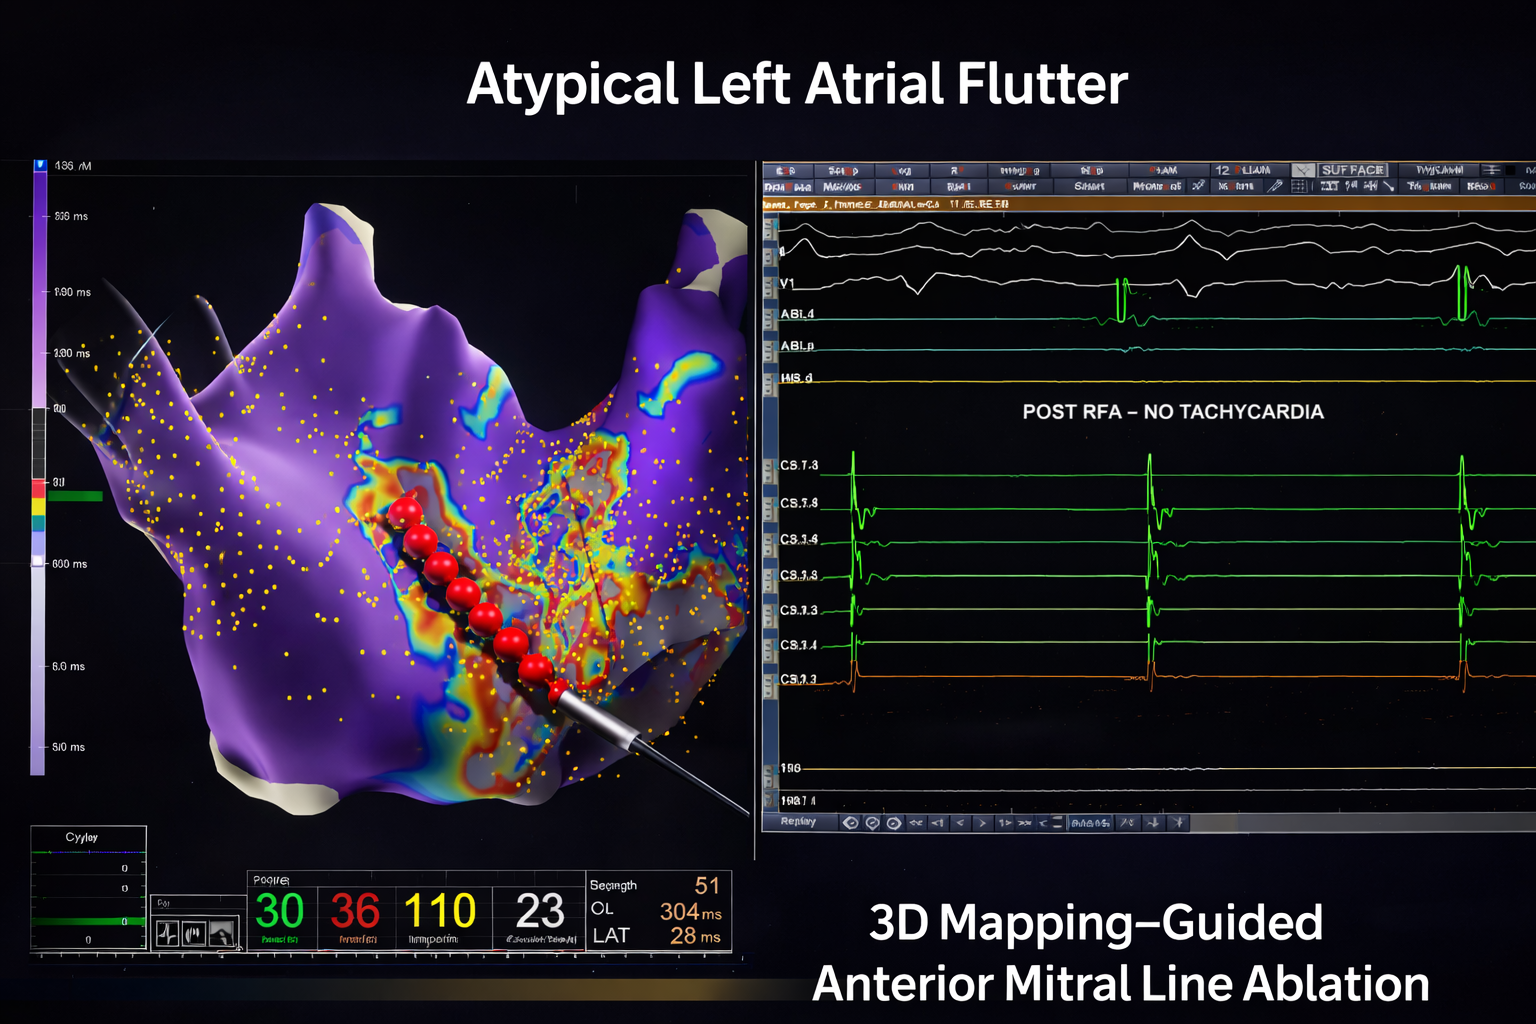

3D LAT Activation Mapping: Identifying the Circuit

LAT activation mapping demonstrated a macro re-entrant circuit in the left atrium.

Key observations:

Activation spanned nearly the entire tachycardia cycle length

High-density grid signals covered approximately 190 ms

The mapping confirmed a scar-related re-entry pattern

Propagation mapping showed wavefront circulation consistent with atypical LA flutter

In post-CABG patients, surgical scarring and atrial remodeling often create slow-conduction channels. These channels act as substrates for re-entry.

The propagation map clearly visualized wavefront movement around a scar region, confirming the arrhythmia was left atrial in origin rather than typical right atrial cavotricuspid isthmus flutter.

High-density mapping revealed:

Fractionated electrograms

Late potentials

Areas of low voltage consistent with atrial scar

These findings are characteristic of atypical LA flutter circuits. Fractionated signals indicate zones of slow conduction — the critical substrate maintaining re-entry.

Ablation Strategy: Correlation with ILAM and Voltage Map

The ablation strategy involved correlating:

Isochronal Late Activation Mapping (ILAM)

Voltage mapping of the left atrium

The critical isthmus was identified along the anterior mitral region.

An anterior mitral line was drawn using an irrigated ablation catheter with:

Power: 35 W

Temperature: 43°C

As shown on, the linear lesion connected anatomical landmarks to interrupt the re-entry circuit permanently.

Creating a complete conduction block across this line is essential to prevent recurrence.

Post-Ablation Assessment

Post-RFA ECG demonstrated sinus rhythm.

No tachycardia could be re-induced.

This confirmed successful ablation and electrical stability.